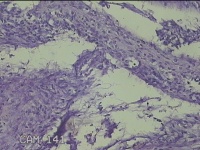

左卵巢囊肿

性别

女

年龄

47岁

临床诊断

左附件囊肿

一般病史

不规则阴道流血20余天。

标本名称

大体所见

灰白暗红色囊壁样组织4.3x1.3x0.3cm一块,表面光滑,因已切开,囊内容物已流失,囊壁厚0.1cm。

良性病变。